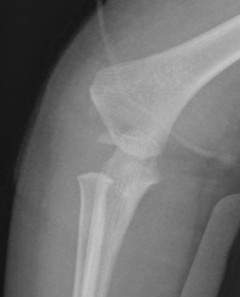

Xray

Distal physis not ossified < 1 year

- radius and ulna lose normal association with distal humerus

- posteromedial displacement of the ulnohumeral joint

- appears like an elbow dislocation

- disruption of radio-capitellar line